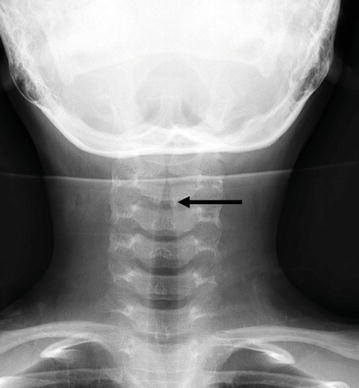

18+ Laryngeal Anatomy Radiology. Kendall the interpretation of laryngeal imaging in the evaluation of patients with voice problems requires a strong foundation in the anatomy and physiology of the larynx. The laryngeal skeleton supports the functional soft tissue structures of the larynx and includes the cricoid, arytenoids, and thyroid.

Test your knowledge on the anatomy of the larynx with this fun. 2 laryngeal anatomy katherine a. The larynx is located within the anterior aspect of the neck, anterior to the inferior portion of the pharynx and superior to the trachea.